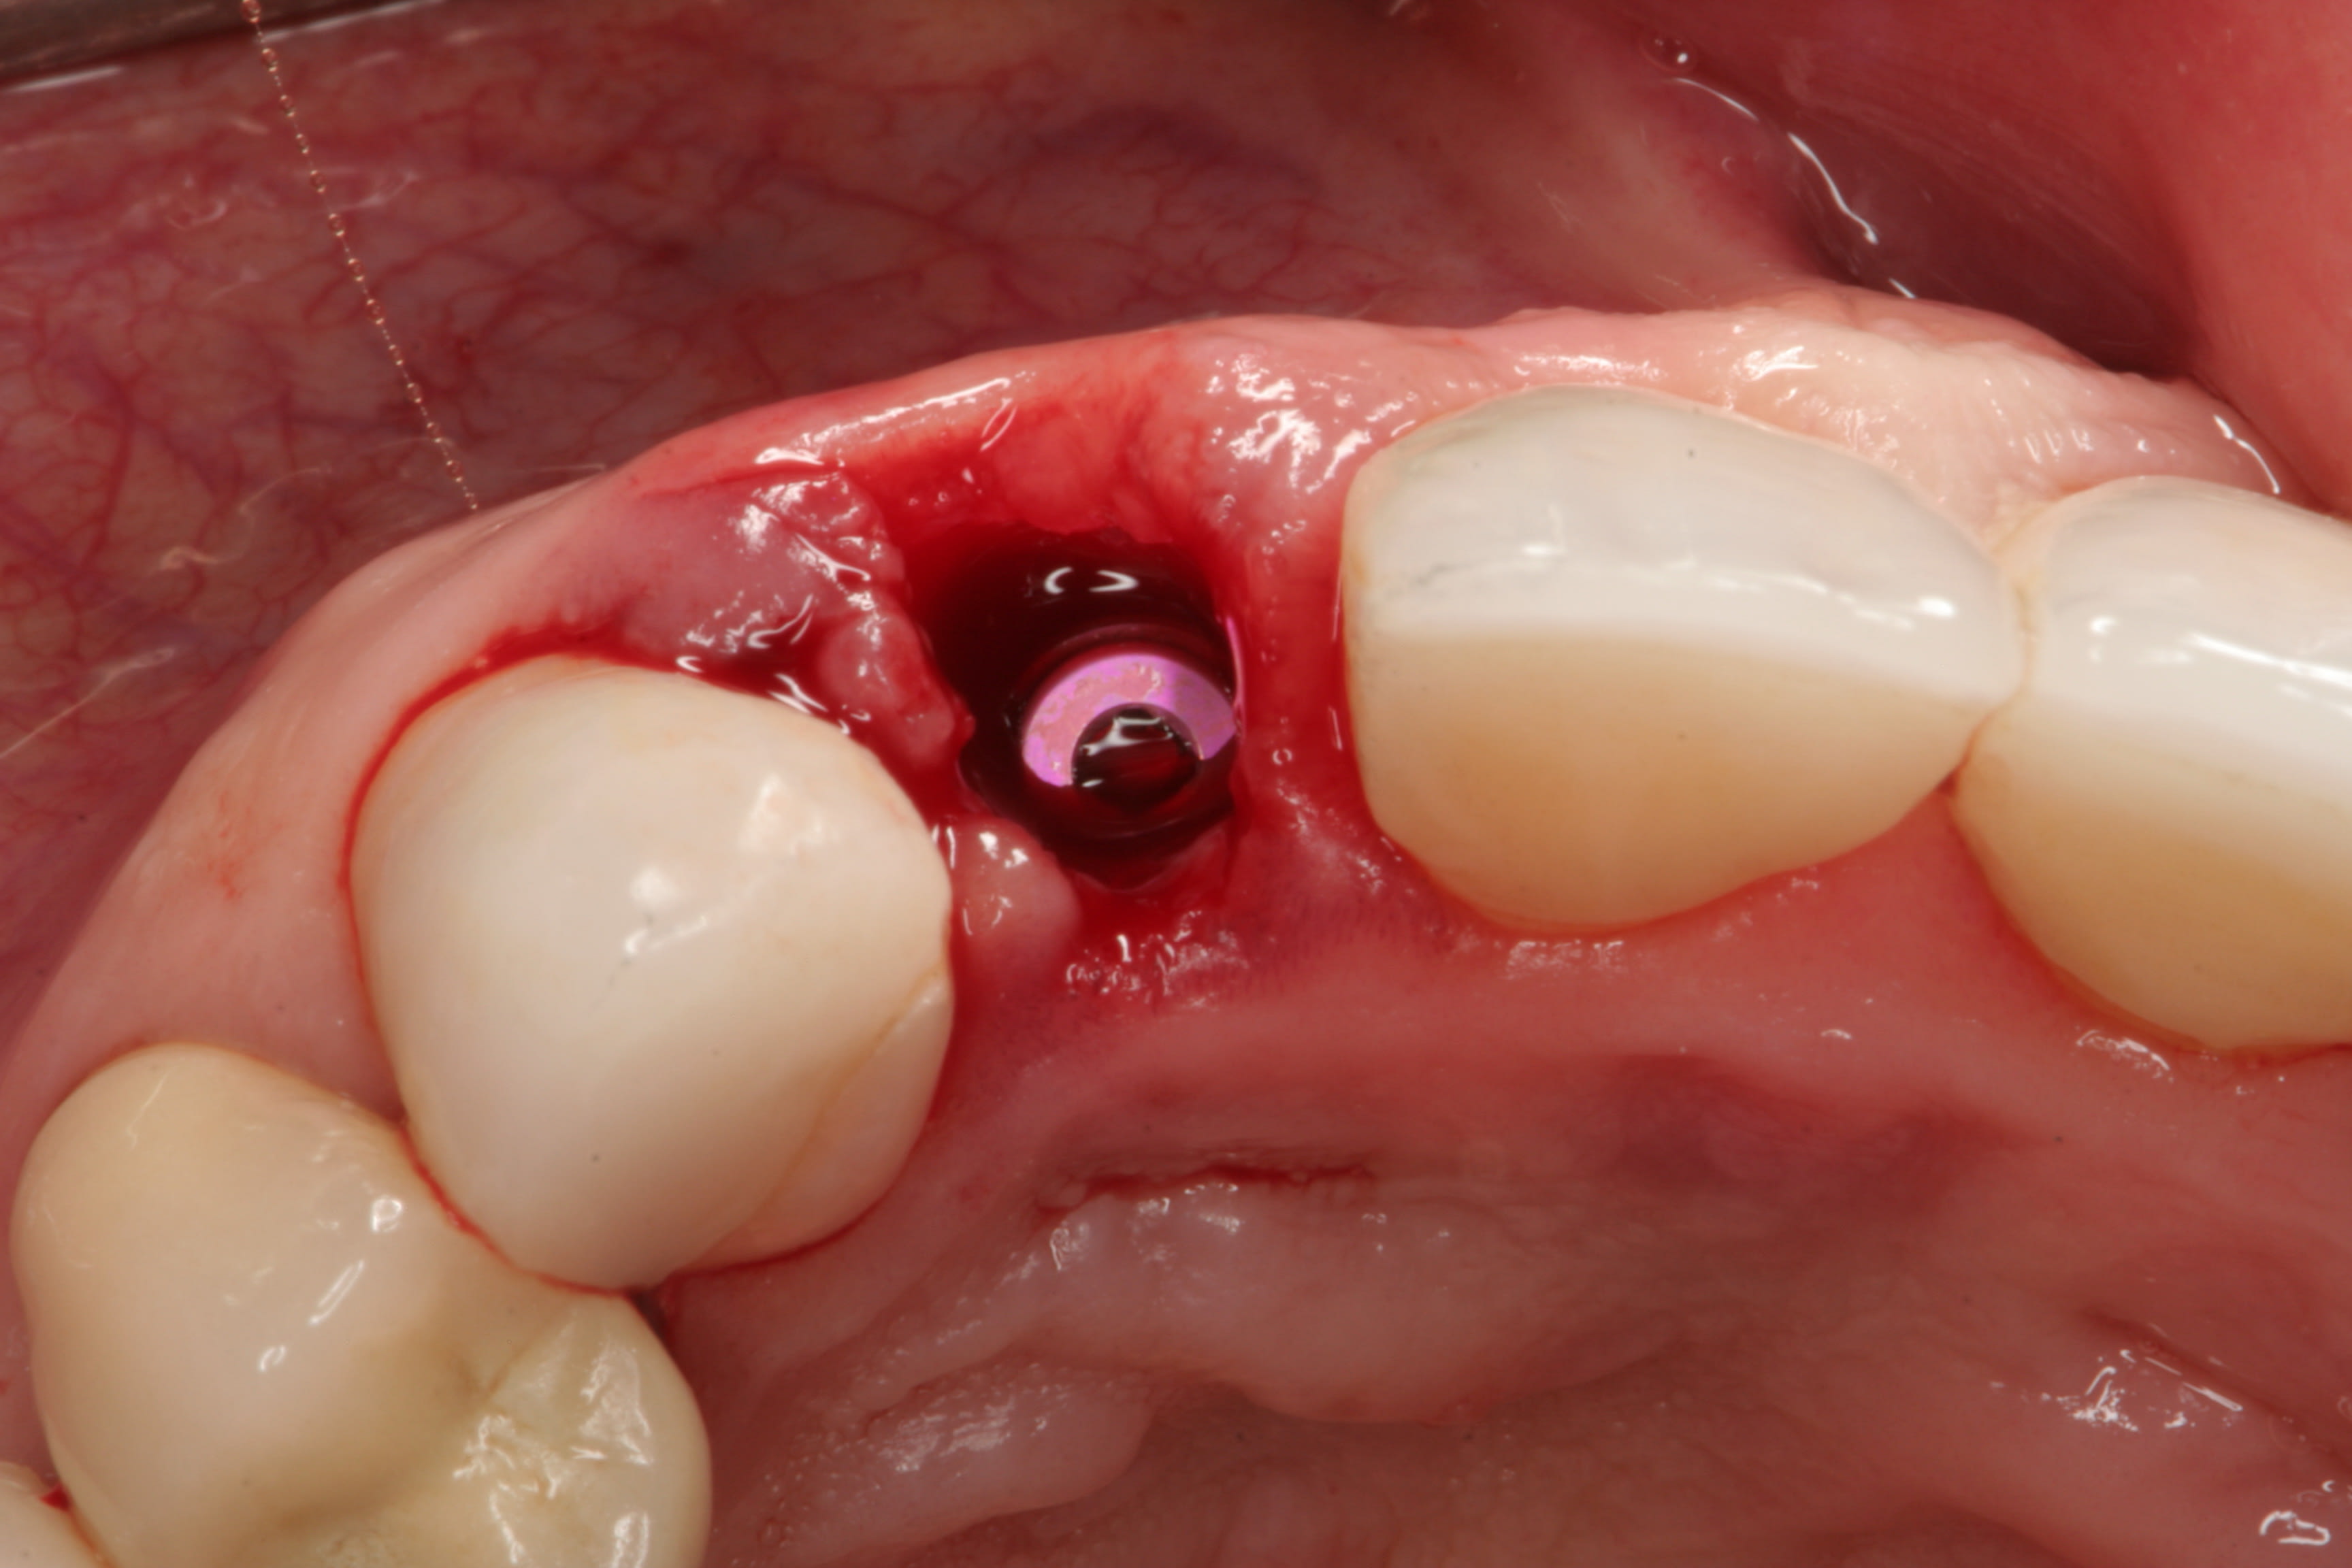

Accordingly, the patient enrolled in the multicenter study in December 2011. She opted for extraction, immediate provisionalization, and immediate loading, and visited both the oral surgeon (JMA) and prosthodontist (MAP) authors’ practices on the same day in January 2012 to consolidate these phases. Teeth Nos. 8 and 9 were extracted under local anesthesia (infiltration with lidocaine 2% with 1:100,000 epinephrine, 3.6 mL). The crowns were removed, then the roots were elevated and extracted. Osteotomy was made in type II (moderate) bone with Class A bone quality; all socket walls were intact. After tapping the sites, two 4.5-mm x 13-mm tapered implants (Genesis) were placed with primary stability of 40 Ncm (Figure 21) and 5-mm healing covers were placed (Figure 22 and Figure 23). The buccal socket gaps were grafted with spongious bone substitute (Bio-Oss®, Geistlich Pharma North America, www.geistlich-na.com). The gingival margins were reapproximated with 4-0 chromic sutures. Postoperative radiographs confirmed proper positioning in the alveolar bone.